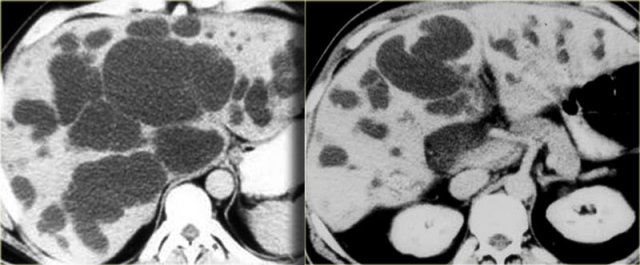

Intrahepatic cholangiocarcinoma

These arise in the very small peripheral ducts.

These tumors have abundant fibrous stroma that can cause retraction of the liver capsule.

The tumor typically enhances in the equilibrium and delayed phases (5-10 minutes).

Although these tumors are usually quite heterogeneous because the contrast uptake is delayed and can be irregular.

The key findings to look for are:

- Delayed enhancement

- Peripheral biliary dilatation

- Capsular contraction

On the left a typical case.

Notice the capsular retraction (blue arrow) and the late enhancement (yellow arrow).